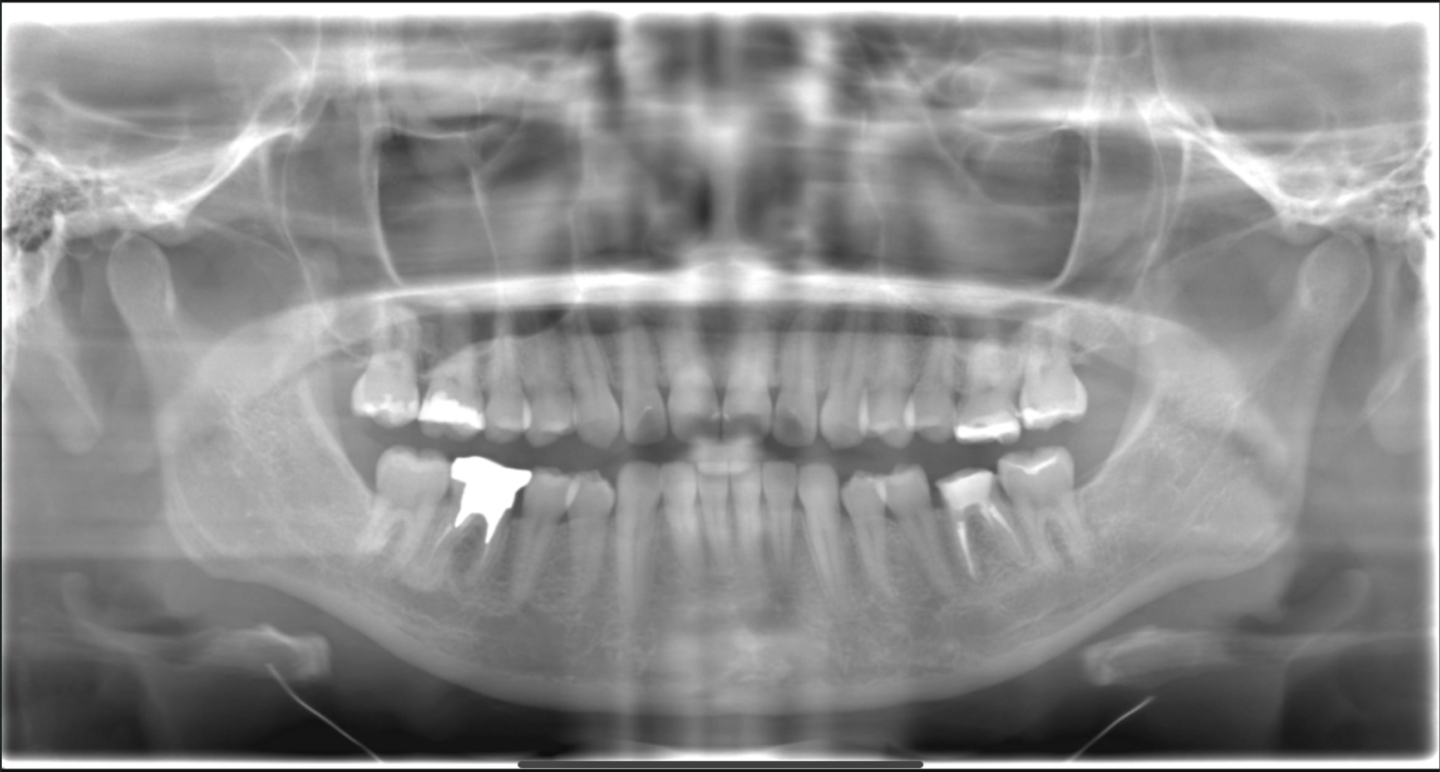

■ 初診時のパノラマ所見

初診時のパノラマレントゲンでは、下顎左右ともに水平埋伏している親知らずが確認できます。

どちらも前方の第二大臼歯に接触しており、特に歯頸部付近で強く当たっている状態でした。